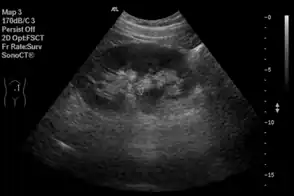

Sistema digestivo

En la ecografía abdominal, se forman imágenes de los órganos sólidos del abdomen como el páncreas, la aorta, la vena cava inferior, el hígado, la vesícula biliar, los conductos biliares, los riñones y el bazo. Las ondas sonoras son bloqueadas por el gas en el intestino y atenuadas en diferentes grados de grasa, por lo que hay capacidades de diagnóstico limitadas en esta área. El apéndice a veces se puede ver cuando se inflama.[19]